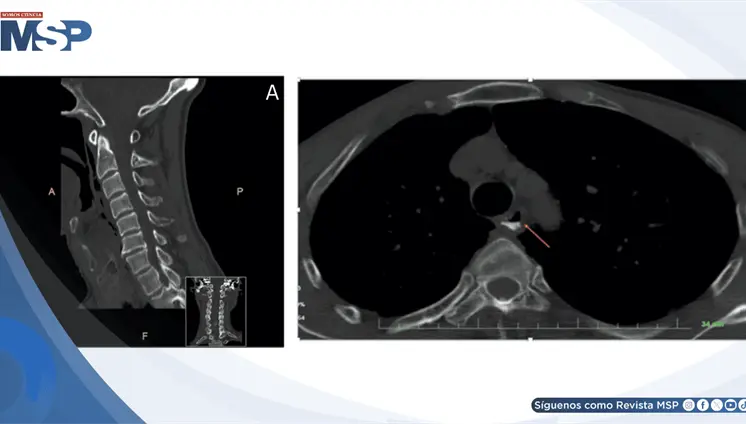

Una mordedura aparentemente menor de perro desencadenó en menos de 48 horas una sepsis grave con shock refractario, síndrome de dificultad respiratoria aguda y fallo multiorgánico. El paciente tenía un bazo reducido y signos de hipoesplenismo funcional.